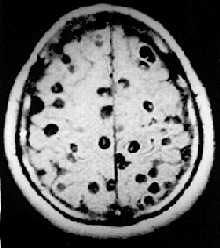

- Neurocysticercosis (NCC): is an infection of the brain or spinal cord caused by the larval stage of the pork tapeworm, Taenia solium. NCC is the most common helminthic (parasitic worm) infestation of the central nervous system worldwide. Humans develop cysticercosis when they ingest eggs of the pork tapeworm via contact with contaminated fecal matter or eating infected vegetables or undercooked pork.[37] "While cysticercosis is endemic in Latin America, it is an emerging disease with increased prevalence in the United States."[38] "The rate of depression in those with neurocysticercosis is higher than in the general population."[39]

CNS Tumors

In addition to pituitary tumors, tumors in various locations in the central nervous system may cause depressive symptoms and be misdiagnosed as depression.[28][69]